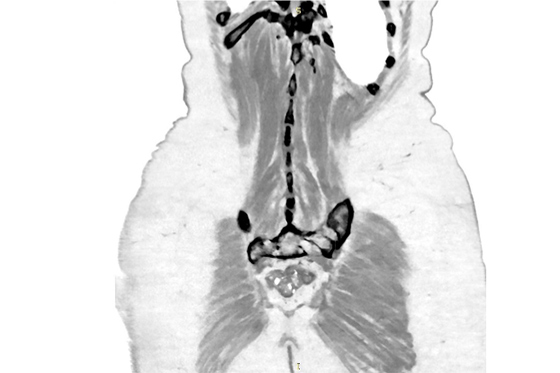

Этот цикл я писал, всматриваясь в медицинские снимки умирающего родного тела. Я пытался разглядеть его изнутри и осознать неосознаваемое: как это — постепенно умирать? Как отпустить, чем отстоять и куда его уложить, чтобы не было больно? В ужасе я наблюдал за расплывающимися узорами смерти, пока она не залила все живые уголки дряхлого тела. Снимки и тексты — свидетельства скрытого, немого страдания, которому я даю право быть увиденным и услышанным.

Это — кадиш по моей бабушке, которая умерла 18 января 2019 года. Была пятница, и похоронить ее нужно было до захода солнца — до начала Шаббата, который наступает в пятничный вечер. Кладбище было напротив больницы, через дорогу. Мы хоронили ее через три часа после смерти, не успев позвать ни родных, ни близких. Кадиш — это иудейская поминальная молитва. Для ее чтения необходим миньян — десять мужчин. Нас было меньше, поэтому хоронили без молитвы, спешно. Эти стихотворения — мой кадиш, который тогда мне произнести не дали, мое отпевание пустоты, что осталась после нее. В кадише использованы реальные медицинские материалы — рентгеновские снимки, УЗИ, КТ, ЭКГ — из истории болезни бабушки, с момента обнаружения рака и до самой смерти. Последняя кардиограмма была снята с мертвого тела. Так требовал больничный протокол.